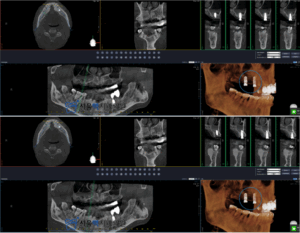

환자분의 상황을 고려하여 어금니 부위 1개,

작은 어금니 부위 1개를

식립하는 계획으로 진행하였는데요.

상악동이 아래 쳐져있어 상악동을 들어올려

그 공간에 뼈 이식한 후

단단하게 임플란트를 식립하는

고난이도의 ‘상악동 거상술’이 필요하였습니니다.

아주 얇은 상악동의 막이 천공되지 않도록

매우 세심하게 진행해야 하는

‘상악동 거상술’과 임플란트의

단단한 유지를 위해 충분히 뼈이식을 해드렸습니다.

임플란트 식립 직 후의 모습으로,

뼈와 임플란트가 잘 유착된 후

치아모양의 보철물을 제작해드릴 계획입니다.